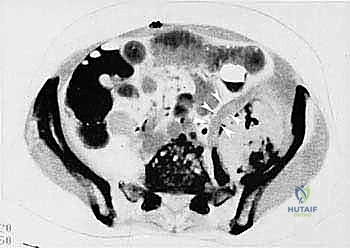

* CT with Intravenous Contrast and 3D Reconstruction (FIG 3): This is our workhorse for assessing bone involvement, destruction, and the critical relationship between the tumor and major pelvic blood vessels. It reveals any distortion of the pelvic anatomy and guides resectability. Figure 3A clearly shows extensive bone destruction and tumor extension into the pelvis and gluteal region. Figure 3C highlights an extensive tumor on the medial aspect of the ilium with destruction of the inner table.